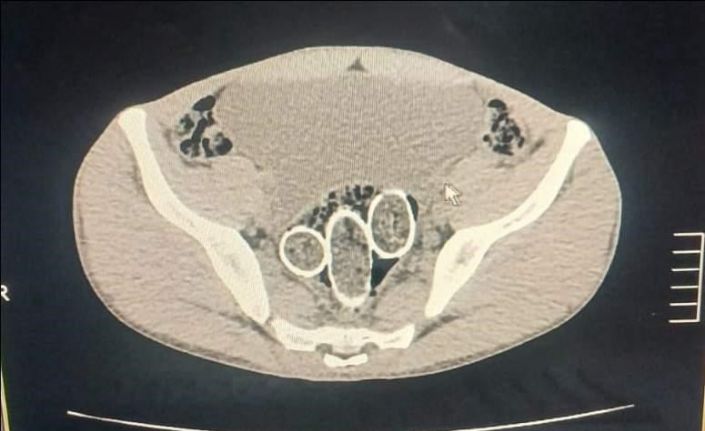

Denizli’de polisin düzenlediği uyuşturucu operasyonunda gözaltına alınan 5 şüpheliden 2’sinin yapılan iç beden muayenesinde rahim ve mideye saklanmış 320 gram uyuşturucu madde ele geçirildi.

Denizli İl Emniyet Müdürlüğü Narkotik Suçlarla Mücadele Şube Müdürlüğü ekiplerince, uyuşturucu ticaret yapan şahıs veya organizasyonların yakalanmasına yönelik operasyon düzenlendi. Düzenlenen eş zamanlı operasyonlarda 5 şüpheli şahıs yakalanırken, iki şahsın yaptırılan iç beden muayenesinde ve kullandıkları iki araçta yapılan incelemelerde rahimde ve midede uyuşturucu madde tespit edildi.

Operasyonda 6 parça halinde 320 gram metamfetamin maddesi, 1,6 gram afyon sakızı maddesi, uyuşturucu madde ticaretinden elde edildiği değerlendirilen 114 bin 430 TL, 12 bin 595 Euro, 300 dolar, 1 adet sahte pasaport ele geçirildi. Ayrıca yakalanan şüpheli şahıslardan 1 şahsın 6 yıl 8 ay kesinleşmiş hapis cezası ve 16 bin 600 TL adli cezası ile arandığı tespit edildi.